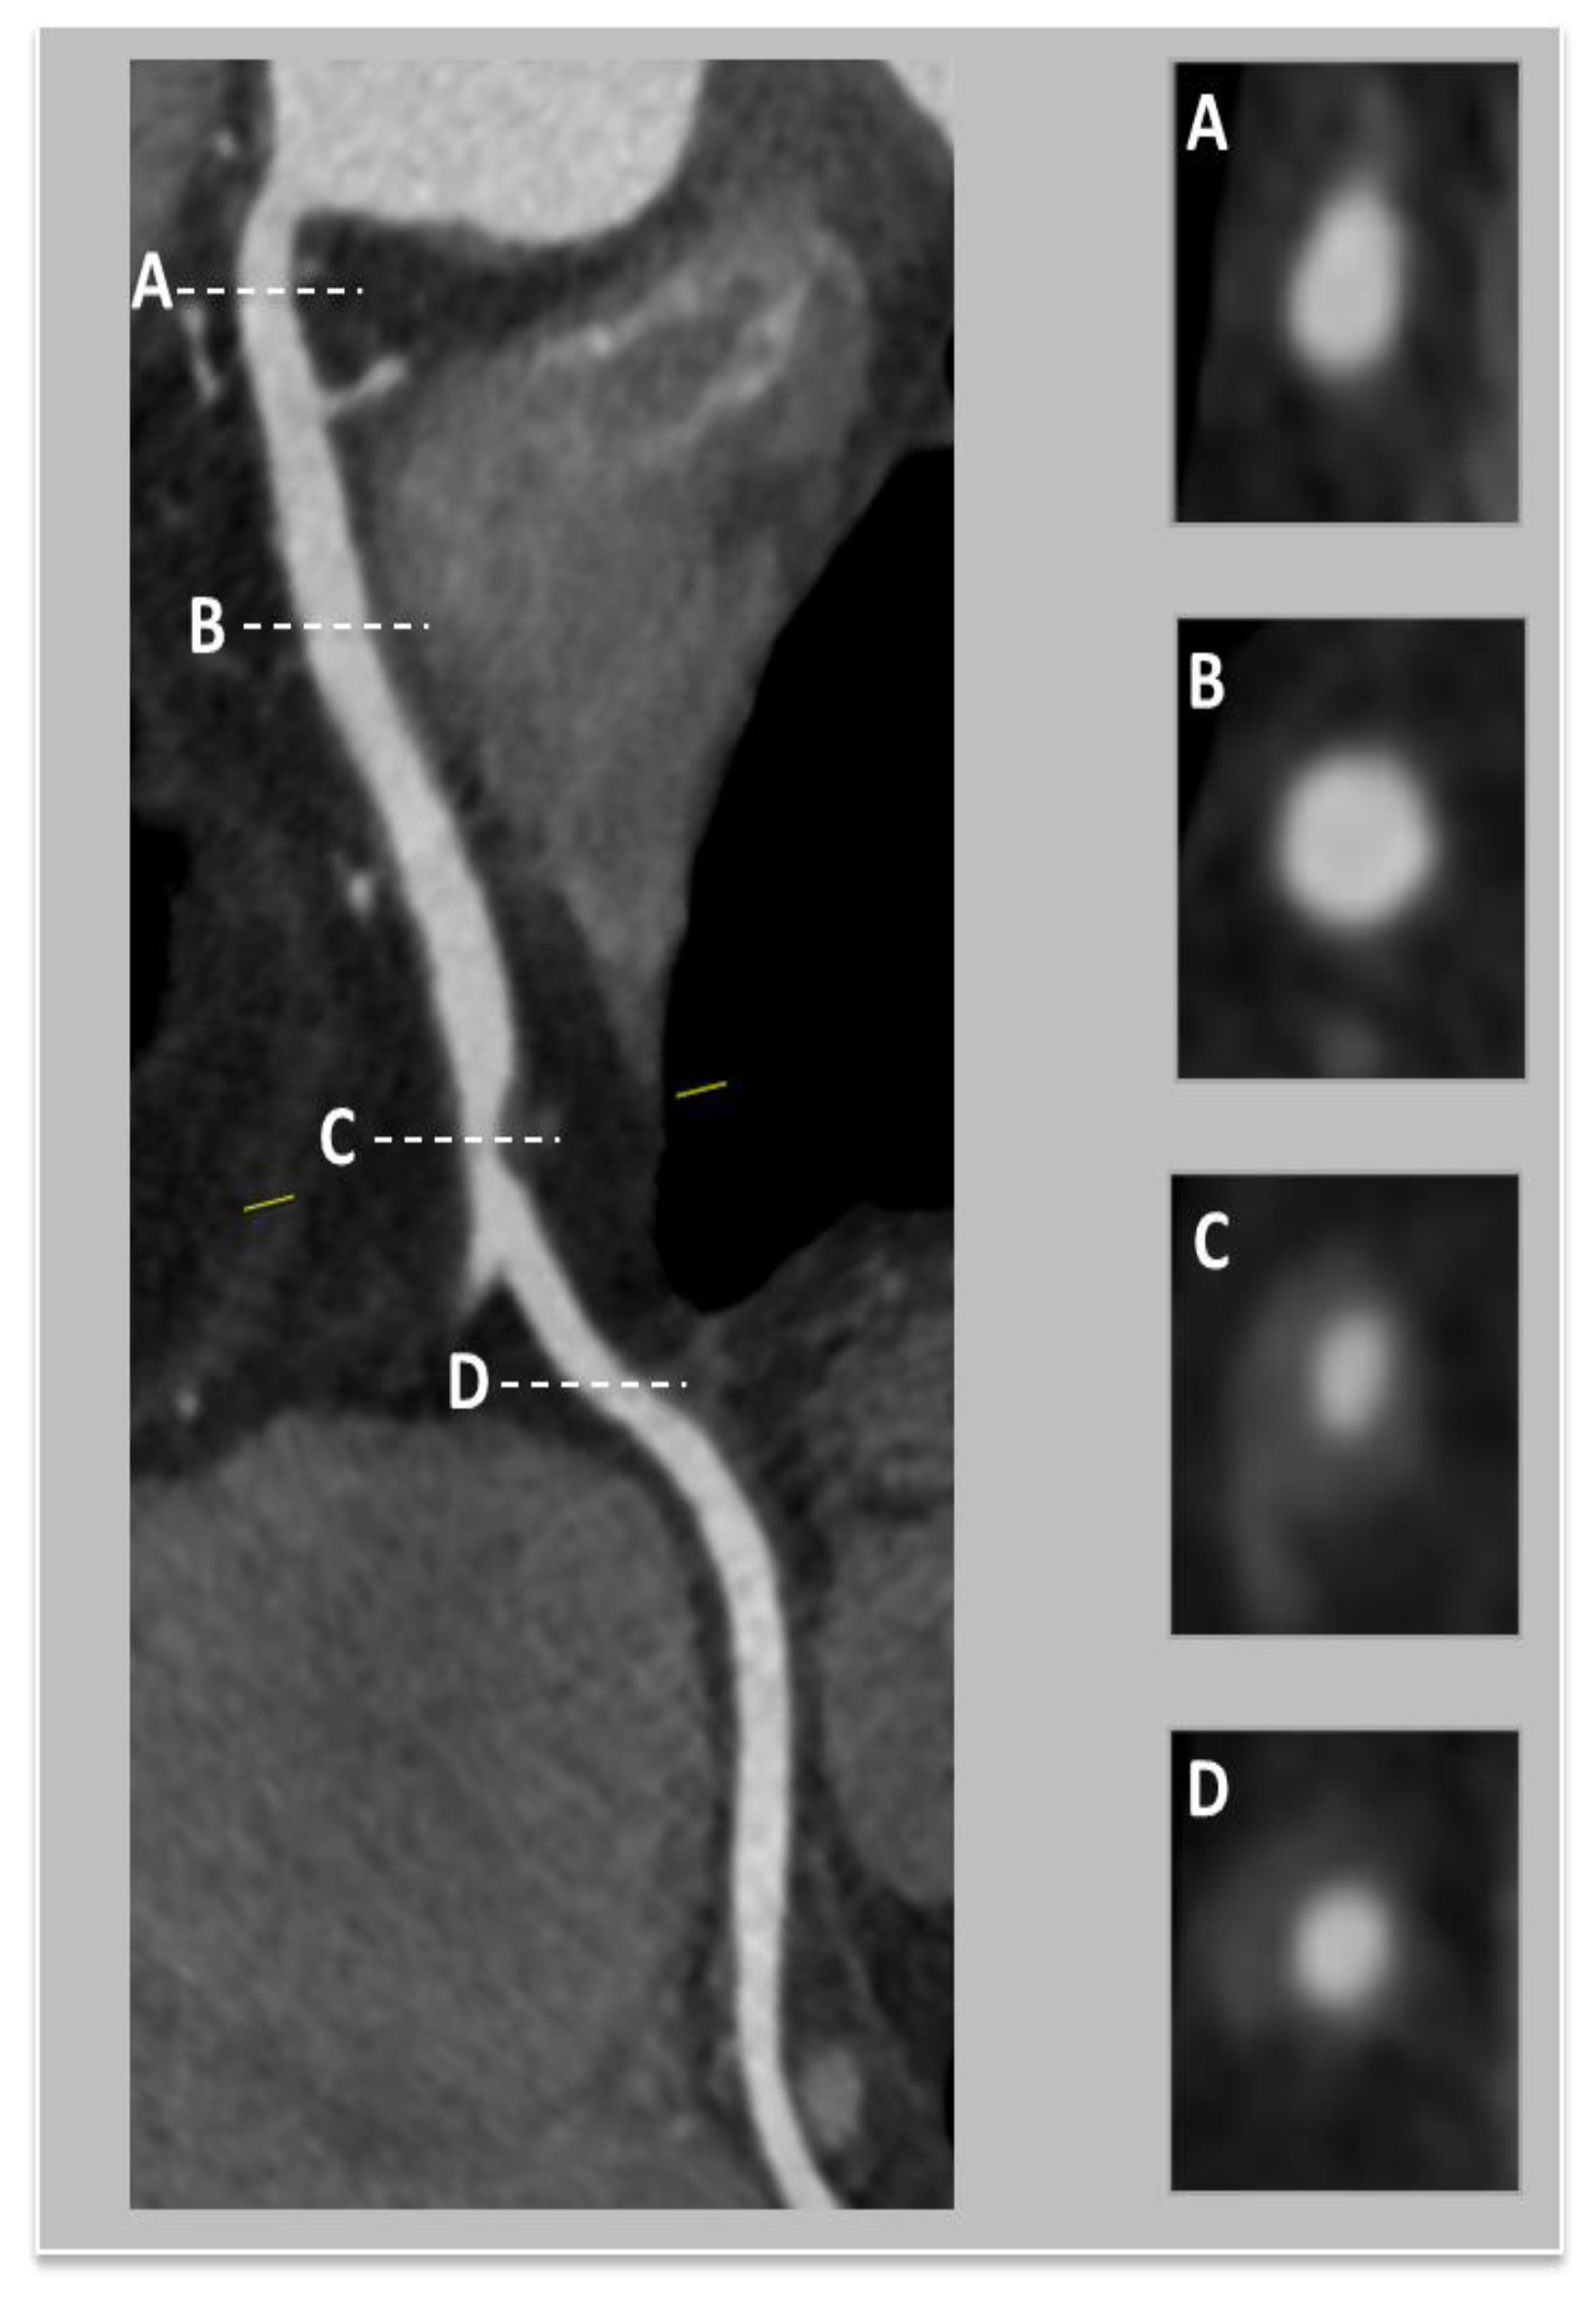

| Coronary computed tomographic angiography (CCTA) | Assess the dimensions and configuration of the arterial wall and lumen Plaque characterization Evaluating the presence, location, and characteristics of aneurysm and stenotic regions Reconstruction of intricate anatomical structures in a three-dimensional model | Noninvasive Greater specificity in cases of aneurysms and thrombosis Suitable for follow-up | Expensive Involves ionizing radiation Requires intravenous contrast media Dependent on an imaging specialist |